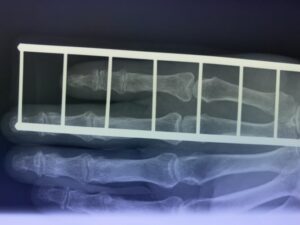

第16回整骨研究会「賜恩」研修会開催

さわやか千葉県民プラザ(指骨骨折)

第18回整骨研究会「賜恩」研修会開催